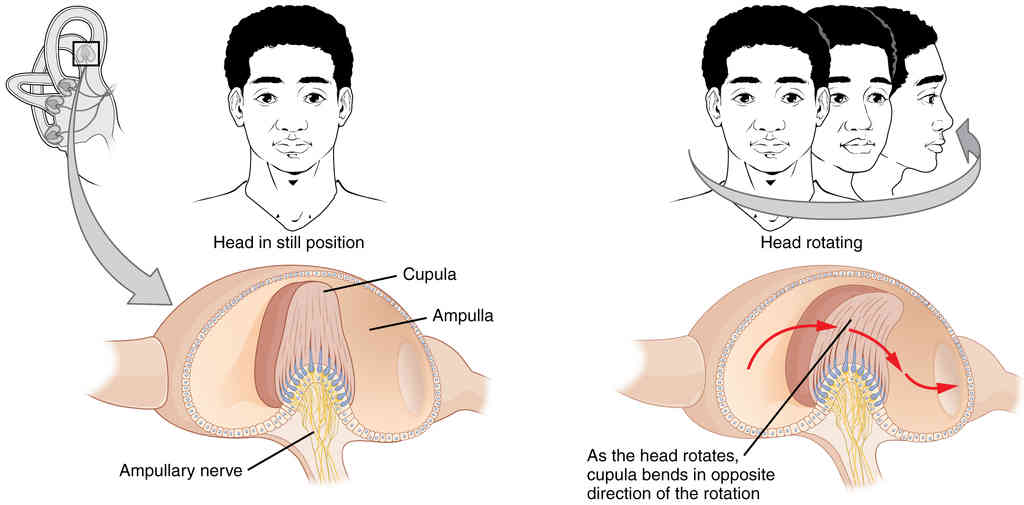

This page is under construction. For now, it is just a resource of the images found in the OpenStax Anatomy and Physiology Handbook. It wil slowly change into a revision tool. Each slide has a number. Use this to refer to the slide. When completed, it will have an unlabelled section, with labelled slides in parallel. On the unlabelled slides, write your answer and use the labelled slide to assess yourself. Keep track by also noting the number on each slide. Improvement at each attempt is important, more so than full marks on a first attempt.